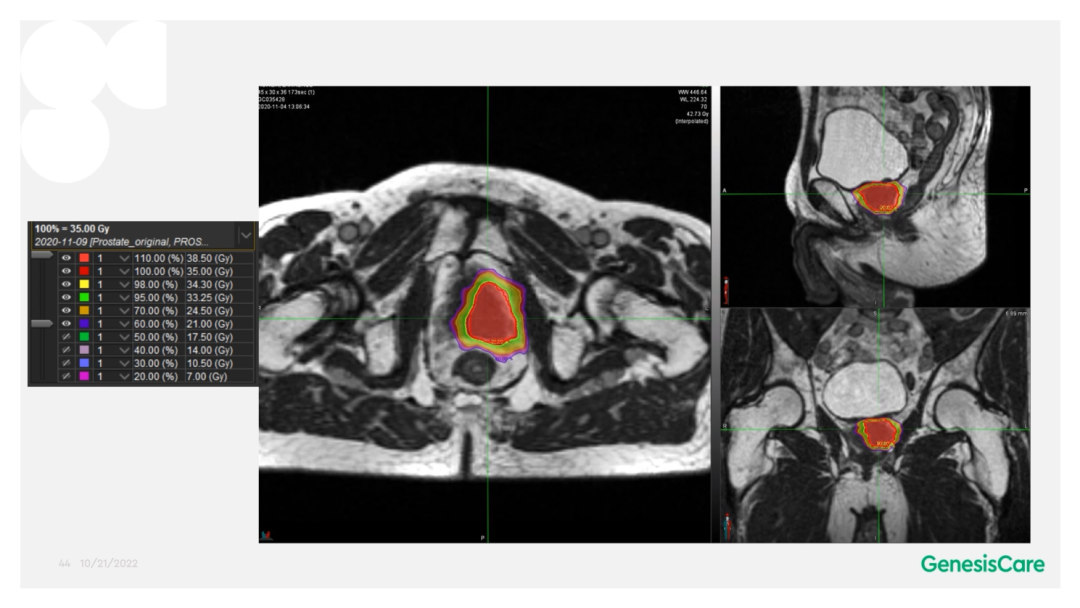

在使用MRIdian以SABR放射消融方式治疗患者不久后,英国就遭遇到了新冠疫情,导致大量放疗中心缩减、停止服务,甚至关停。GenesisCare在疫情期间为就诊的所有前列腺癌患者,都进行5个分次的SABR放射消融治疗。第一年使用的剂量分割为36.25Gy/5F,第二年升级了规程,在保护危及器官的基础上,给予靶区内同步推量至CTV 40Gy/5F,PTV 36.25Gy/5F。

Dr. Camilleri表示,他们在做在线自适应放疗的时候,为了提高速度,仅对靶区外放3cm以内的危及器官的变化进行自适应调整或重新勾画轮廓,见Figure 13。这样可以缩短轮廓勾画的时间。对于放疗计划,使得95%的靶区体积接受到100%的处方剂量覆盖,并将最大剂量限制为2%的靶区体积不超过处方剂量的110%,这样就能保证在图像上很难显示的尿道不会超量,见Figure 14。另外,在制作放疗计划时,将PTV分为PTV LOW和PTV High,PTV和危及器官重叠的部分为PTV LOW,将PTV LOW的剂量目标设定在危及器官的耐受剂量以下,这样就能保证危及器官不超量,见Figure 15。